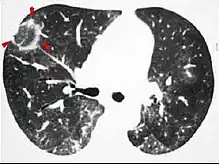

Signe de halo inversé

Un signe de halo inversé est une opacité centrale « en verre dépoli » entourée d'une consolidation plus dense.

Les critères de ce signe incluent que la consolidation doit former plus des trois quarts d'un cercle et avoir une épaisseur d'au moins 2 mm[1].

Significations possibles :

- probable bronchiolite oblitérante avec organisation pneumonique[2], mais ce signe n'est observée que chez environ 20% des personnes atteintes de cette maladie[1] ;

- infarctus pulmonaire (généralement consécutif à une embolie pulmonaire) où le halo est créé par des hémorragies dans le poumon[3] ;

- certaines maladies infectieuses telles que la paracoccidioïdomycose, la tuberculose, la zygomycose ou l’aspergillose, ainsi que la granulomatose avec polyangéite, la granulomatose lymphomatoïde et la sarcoïdose[4].